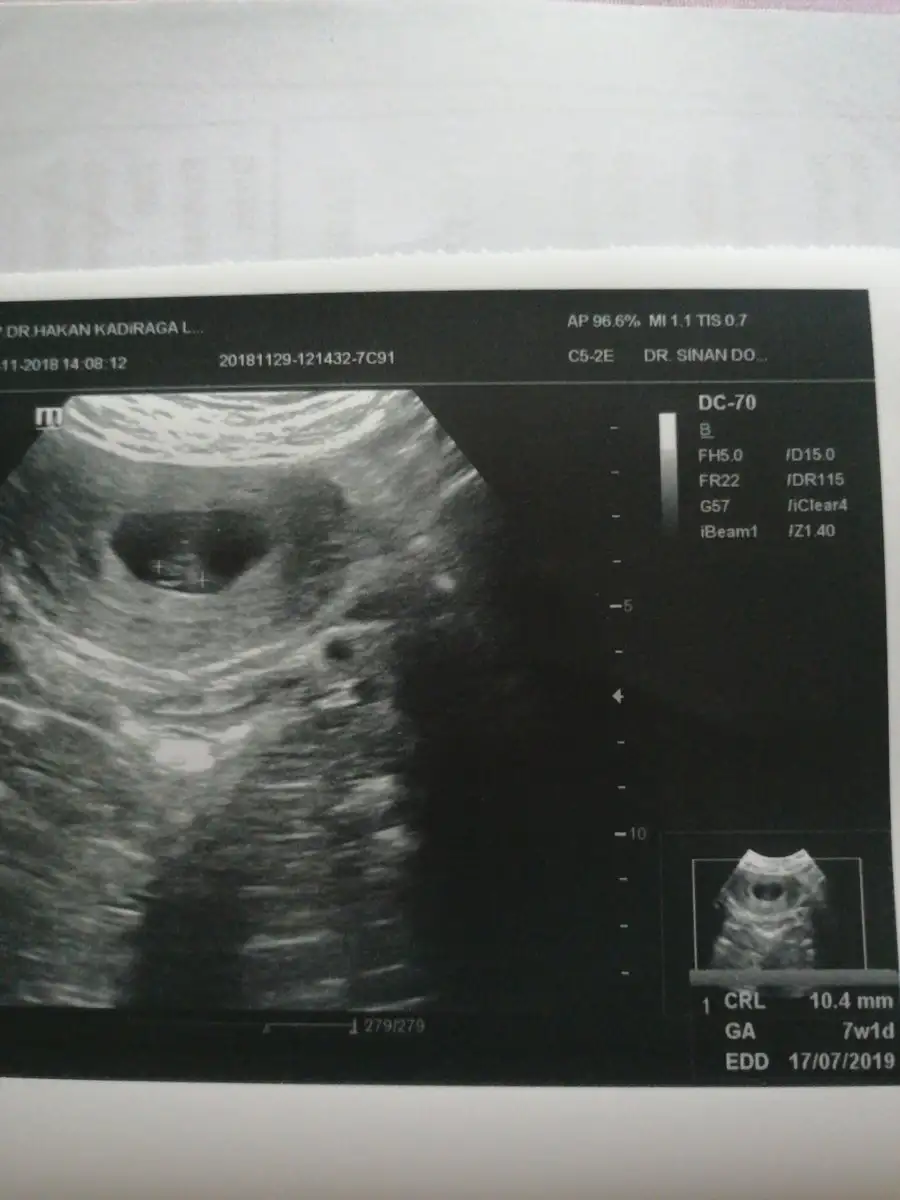

Aaaaa ikiz bunlar, içinde bebelerde var. Rabbim saglıkla kucağına almayı da nasip etsin inşallah, çok sevindimUltrason cihazida biraz eskiydi kagitta cok detayli degl. Benim doktormda gunum 6+5 bugun cihaz kaynkli frkli ciksbilir blki. Bi kagitta 6+3 birinde 6+4 yaziyo. 2 farkli sayi da garip gldi. Cikti verdi ekledim kizlar ben cok anlamiyorm yeni tecrube ediyorum ilk bebegim bilginiz varsa yazarsaniz cok sevinirim❤ bnde tedaviden kalan kistler ve yumrta vrdi onlar sandim ben ilk icini gostrnce ikilemde kaldim. Haftaya gidicem bakalim. Hepsine kabuluz Allahim neyi nasip ettiyse![]()